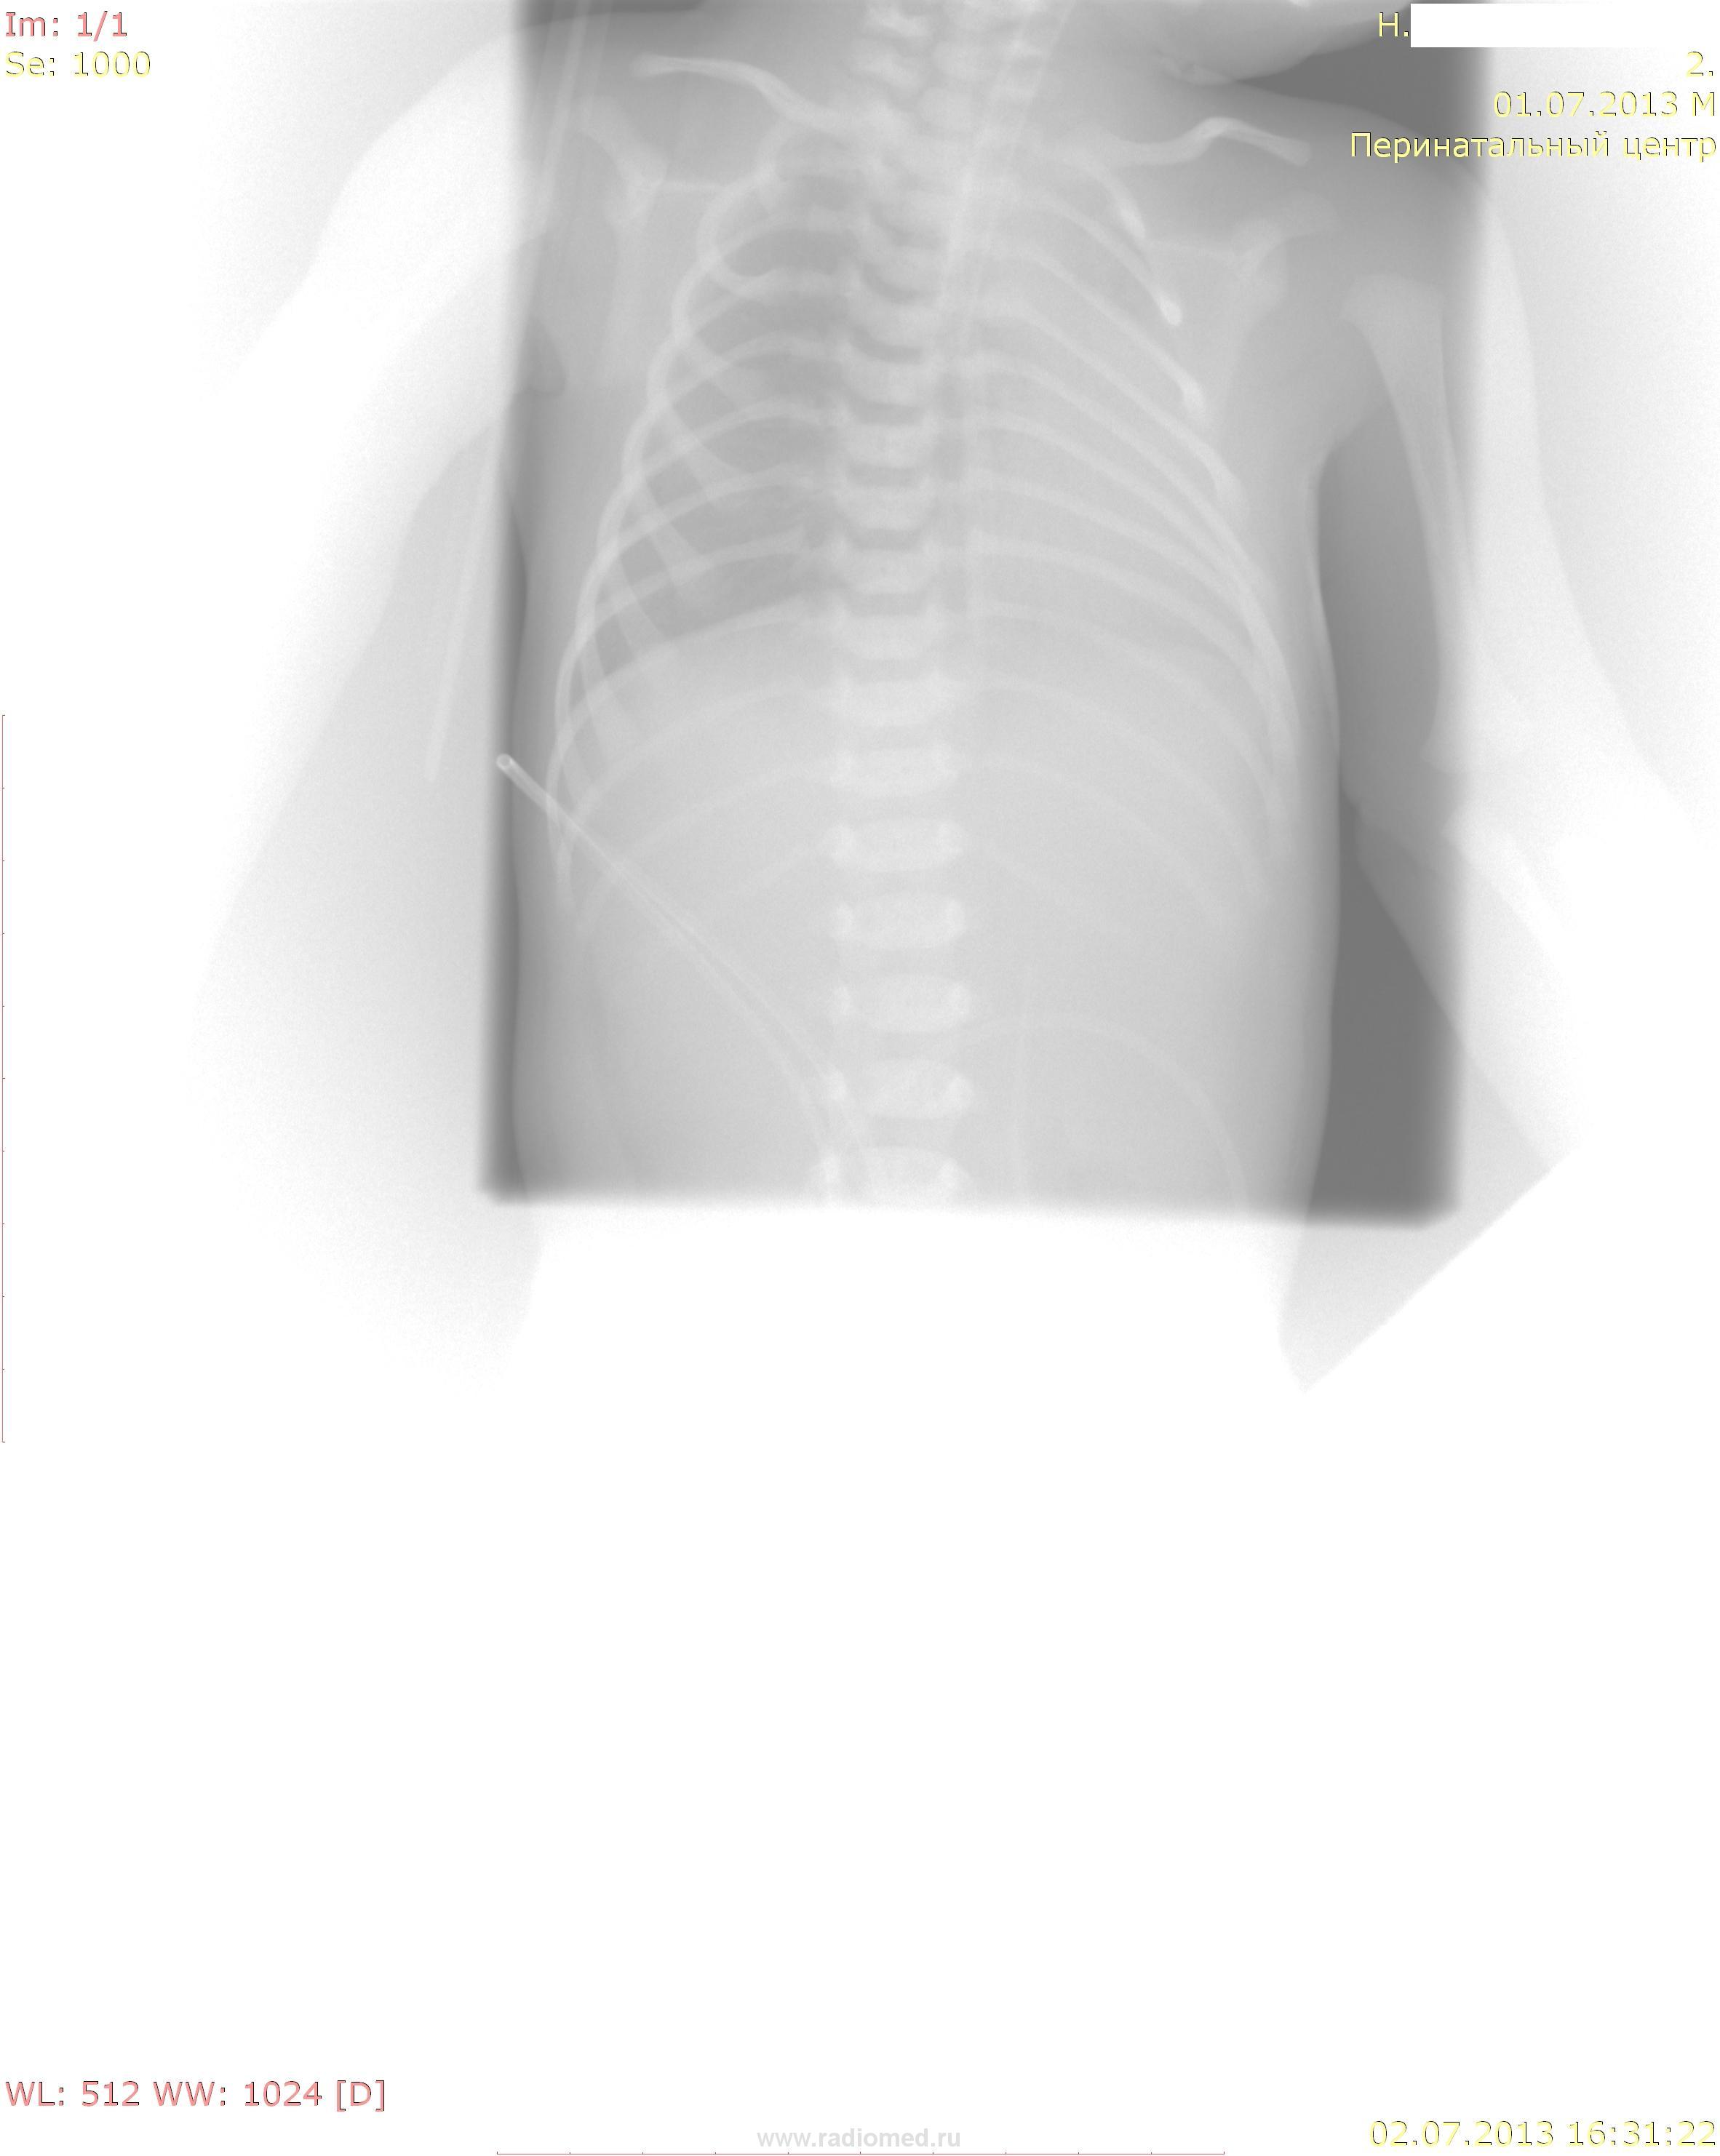

Расценил бы как ателектаз левого легкого. А со снимками надо что-то делать, коллега: и укладка не очень (почему не пересняли?) и режимы.

Андрей Юрьевич, я то же написал в протоколе ателектаз левого лёгкого? Это цифровой снимок: на манитрое компьтера, его можно довести до неплохого качества, как отредатровть и сохранить такое качество на сайте, я не знаю. В отношении укладки, это тяжелейший ребенок по состоянию, находится на аппарате ИВЛ ( в этом, вероятно причина ателетаза,т.к. трубка низковата расположена) и двигать такого пациента микропедиатры просто запрещают.